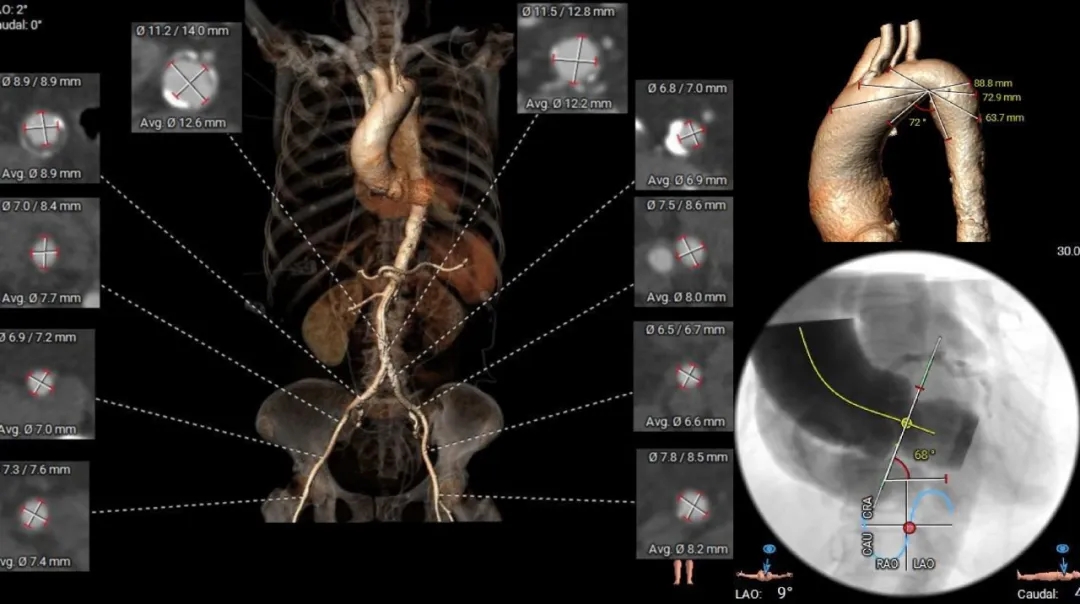

主动脉根部测量

Annulus

21.9mm

LVOT

22.3mm

钙化积分

715mm3

STJ

34.9mm

AAO

42.2mm

SOV

30.4mm*37mm

瓣上结构测量

Super-Annulus 2mm 23.2mm

Super-Annulus 4mm 23.4mm

Super-Annulus 6mm 24.2mm

Super-Annulus 8mm 24.7mm

冠脉风险评估

Left Coronary

LCA & Leaflet

Right Coronary

RCA & Leaflet

-

左、右冠脉高度尚可

双侧瓣叶不长

结合SOV、STJ内径评估冠脉风险不高

左室测量

心室内径尚可

心室壁增厚

外周入路评估

外周血管内径充足,少量钙化斑块

68°横位心